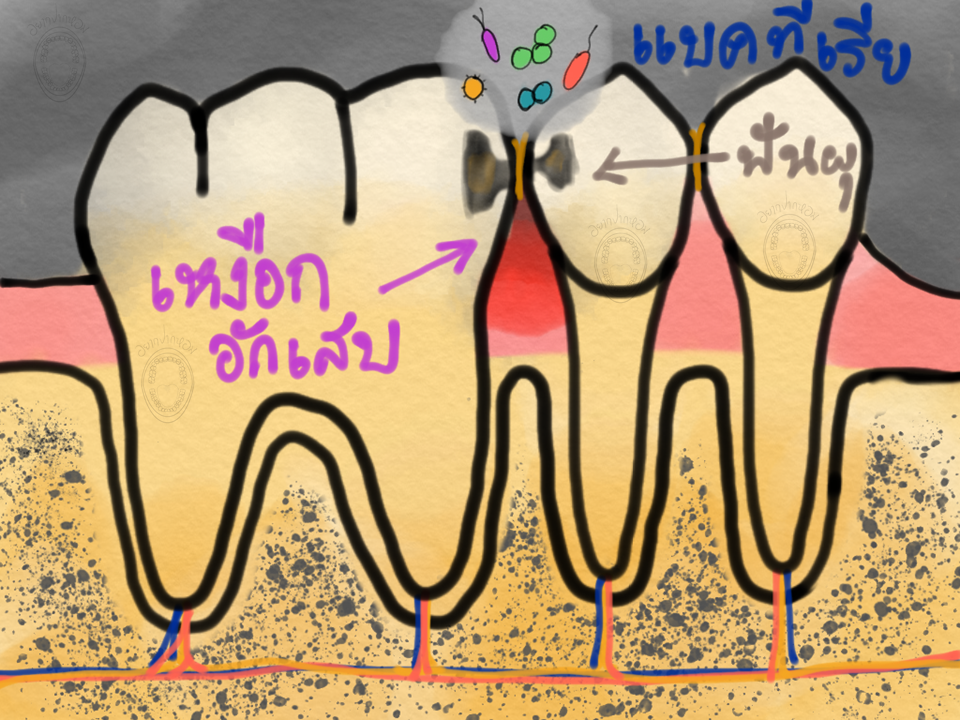

อยากให้ทุกคนลองจินตนาการ เวลาเราแปรงฟันทุกวันๆ ถูฟันเราอยู่ทุกวัน แล้วเราเคยสงสัยไหมว่า แล้วตรงซอกฟันหละ? ขนแปรงมันไม่มีทางเข้าไปถึงซอกฟันแน่ๆ เราจะทำความสะอาดยังไงได้หละ? หากเราไม่ทำความสะอาดตรงซอกฟันเหมือนที่เราแปรงฟันทุกวันๆ คราบฟันที่เข้าไปติดตรงนั้น ตรงที่เราแปรงเข้าไปไม่ถึง มันจะเป็นยังไงกันหละ?

แน่นอนครับ สมมติว่าเราไม่เคยใช้ไหมขัดฟันเลย พอมันอยู่บนฟันเรานานๆ ทำความสะอาดไม่ได้เลยเป็นเวลานานหลายปี คราบฟันที่ไปติดตามซอก ซึ่งอุดมไปด้วยเชื้อแบคทีเรียก็จะเริ่มทำงาน แบคทีเรียเหล่านี้จะเพิ่มจำนวนมากขึ้น เพราะสิ่งแวดล้อมที่เหมาะสมทำให้มันแบ่งตัวเพิ่มขึ้น หลังจากนั้นแบคทีเรียก็จะเริ่ม ทำร้ายผิวฟันด้านซอกฟัน ทำให้เกิดความเสี่ยงต่อการเกิดฟันผุซอกฟัน ทำร้ายเหงือกที่อยู่ใกล้ซอกฟัน ทำให้กระดูกรอบฟันร่นลงไปได้ นอกจากนี้ หากเราไม่ทำความสะอาดซอกฟันและมีคราบฟันเกาะอยู่มากๆ ยาสีฟันที่เราอุส่าเลือกมาซึ่งมีฟลูออไรด์อยู่มากที่จะมาช่วยป้องกันฟันผุให้เรา สุดท้ายยาสีฟันมันก็จะไปช่วยลดฟันผุให้เราตรงซอกฟันไมได้ เราก็คงต้องเสียเนื้อฟันของเราไป หรือบางคนละเลยตรงนี้ สุดท้ายก็จบด้วยการถอนฟัน

จากเหตุผลที่ผมได้เล่าไปแล้ว เราจึงต้องทำความสะอาดซอกฟันทุกซอกในช่องปากของเราให้ได้ครับ เพื่อทำให้ฟันและเหงือก สุขภาพดีตลอดเวลา